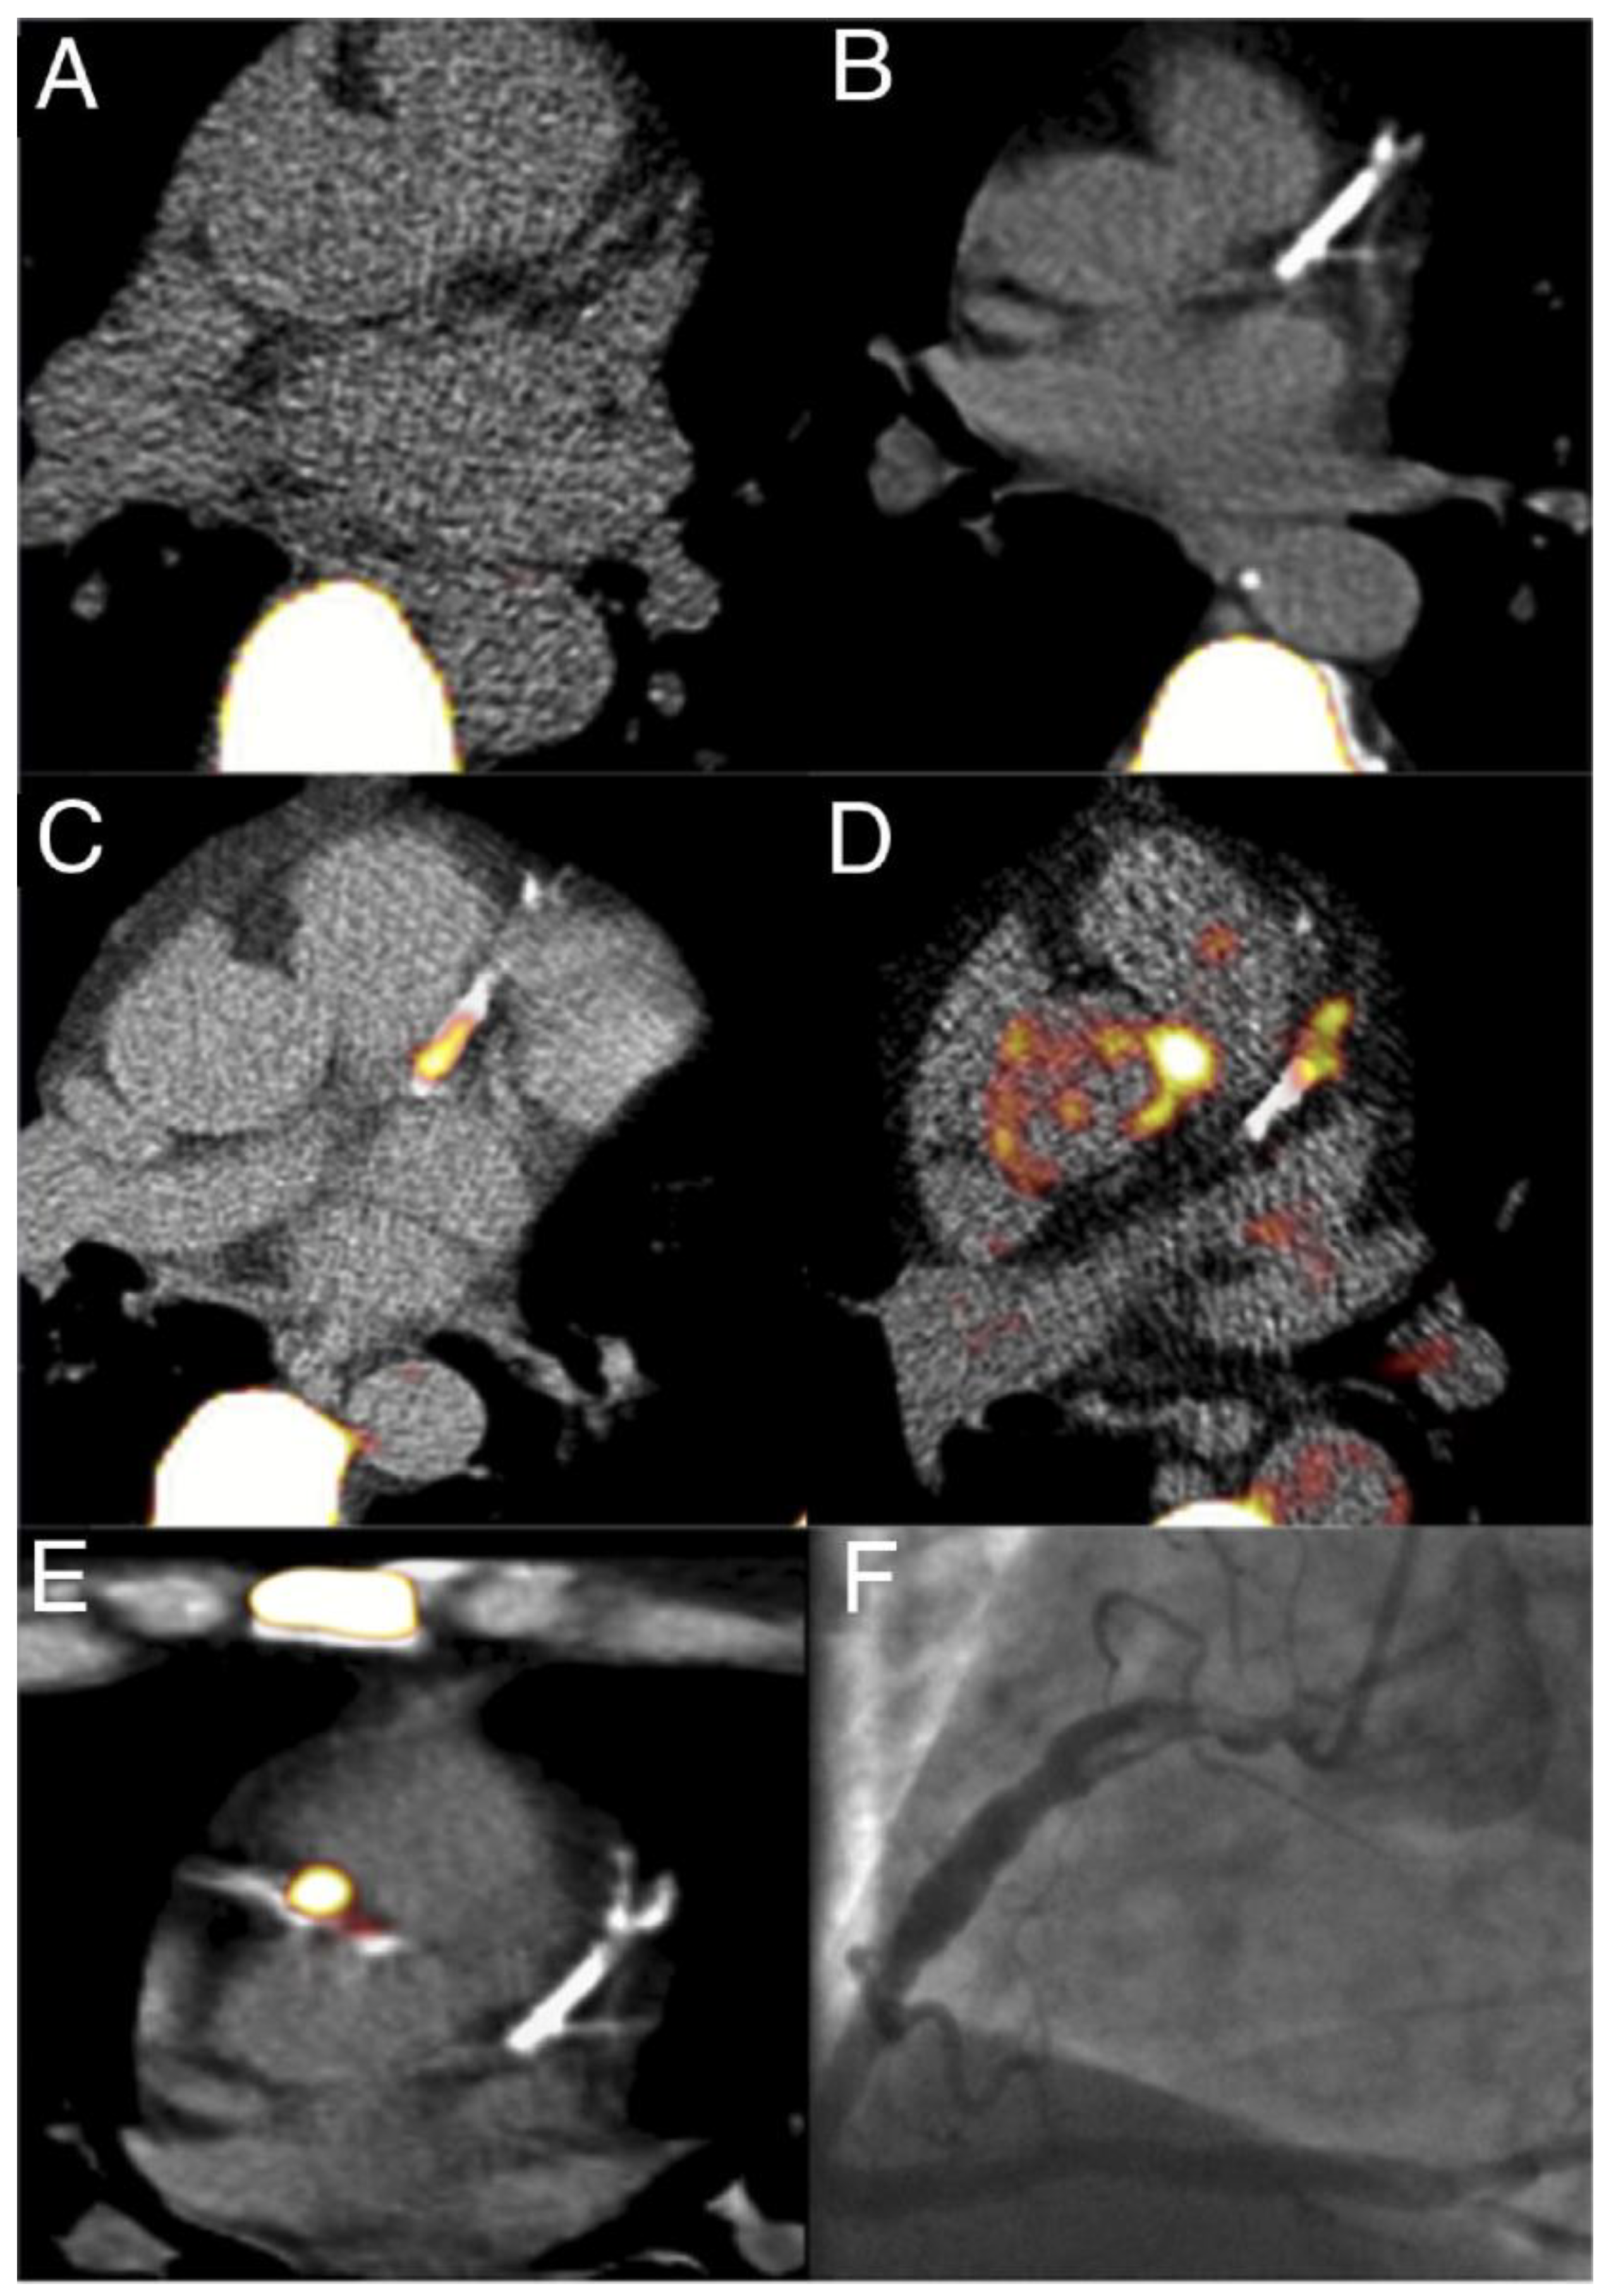

1.5. Micro-Calcifications

- Coronary plaque specificity is demonstrated to be exceptional for detecting micro-calcification in coronary atherosclerotic plaques by 18F NaF, a hallmark of vulnerable lesions. This specificity arises from the ability of 18F NaF to reflect the exchange of hydroxyl groups in hydroxyapatite crystals, which is a crucial step in the calcification process of coronary plaques.

- Coronary imaging challenges due to their small size, constant motion, and proximity to the metabolically active myocardium is overcome by 18F NaF to provide:

- Low background activity due to rapid clearance of 18F NaF from the circulation, resulting in minimal background activity in the myocardium even after just 1 h. This allows for accurate quantification of coronary plaque uptake without complex target-to-background ratio measurements.

- Superior coronary visualization because the low myocardial uptake of 18F NaF enables clear visualization of coronary plaques.

- Early detection of vulnerable coronary plaques because 18F NaF accumulation in micro-calcification before visibility on CT, allowing earlier intervention. Furthermore, 18F NaF uptake can differentiate between active and indolent calcification in coronary arteries, providing crucial information on plaque activity and potential instability.